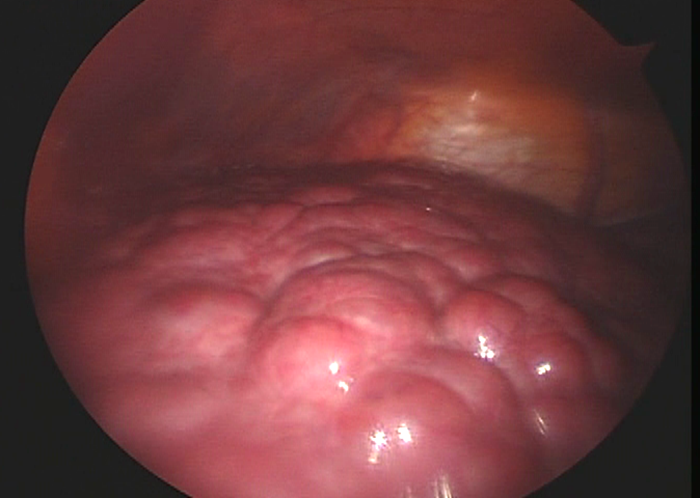

- 영상 검사 : 초음파, CT, MRI 등을 통해 간의 상태를 시각적으로 평가합니다.

- 간 생검 : 필요시 조직 검사를 통해 간의 구조적 변화를 확인할 수 있습니다.